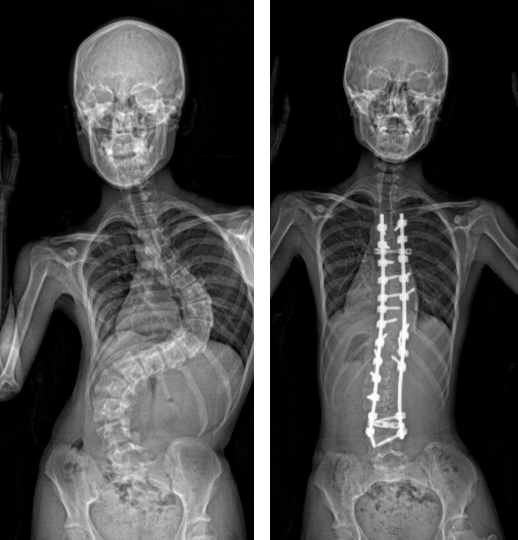

【脊柱側彎成因】港大研究:因「SLC6A9 基因」出現變異 有助為患者提供預防性治療

原發性脊柱側彎是最常見的脊柱畸形,影響全球數以百萬青少年。港大研究團隊最新發現,原發性脊柱側彎主要成因,是「SLC6A9 基因」的出現變異,令神經訊號的傳遞和協調中斷,以及負責步行或呼吸等自主行為的「中樞模式發生器」失調,有關研究已在學術期刊《臨床研究期刊》發表。

脊柱側彎於青春期時惡化

本港有3.5%介乎10歲至18歲的青少年為AIS患者。脊柱側彎一般於青春期時惡化,可導致各種併發症,包括心肺功能受損、呼吸困難,或有背痛、高低膊、盤骨不對稱,造成外觀問題,有可能影響患者的社交活動和心理健康。